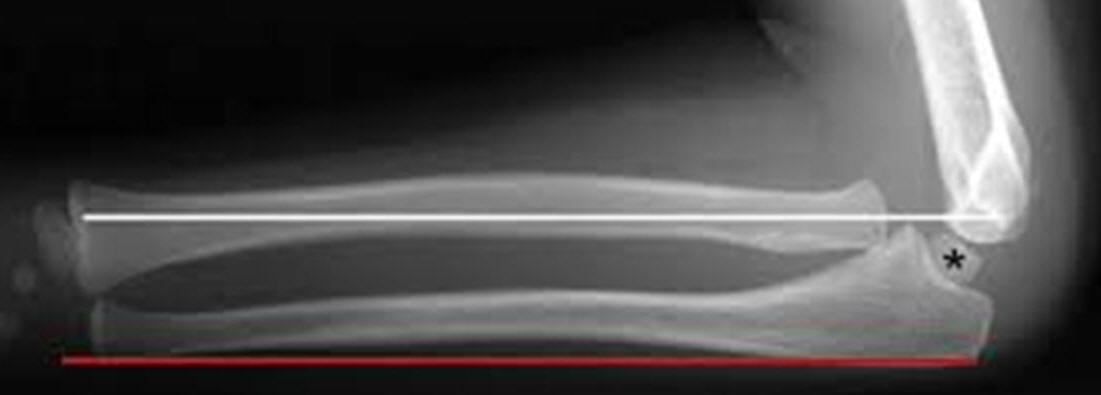

Undersiden af ulna skal være helt lige:

Ved en bowing ulna ses ofte caput radii luksation: